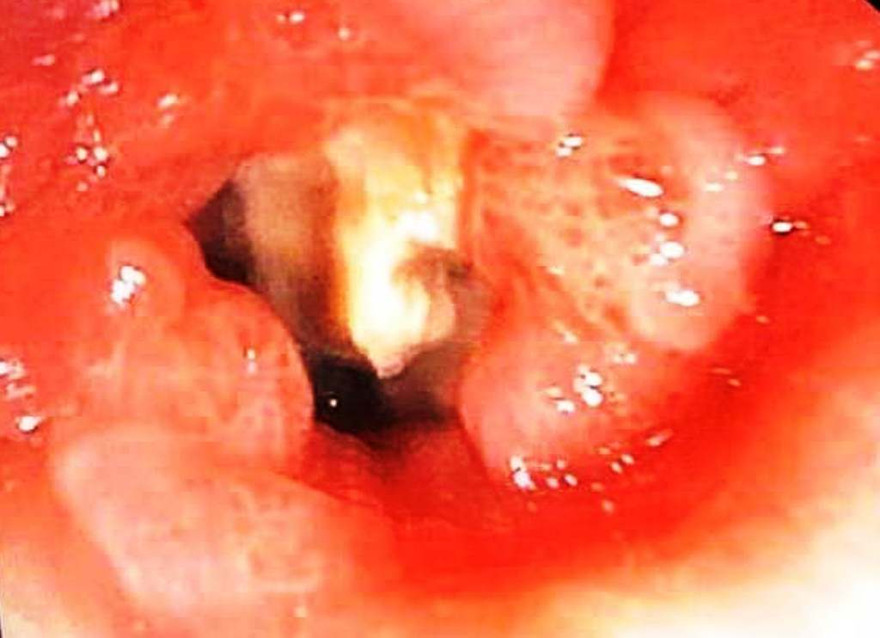

Trước đó, bệnh nhân Nguyễn Ngọc Đ. (74 tuổi, ngụ Hương Phong, thị xã Hương Trà, TT-Huế) nhập viện với triệu chứng ho, khạc đờm, khó thở đã kéo dài 1 tháng; được chẩn đoán viêm phổi, tràn dịch màng phổi trái, bệnh phổi tắc nghẽn mạn tính. Bệnh nhân được làm các xét nghiệm, nội soi phế quản ống mềm và nghi ngờ có dị vật ở phế quản thùy dưới trái, vị trí tiếp xúc của dị vật tăng sinh mô hạt nhiều; niêm mạc phế quản thùy dưới viêm đỏ, phù nề; có nhiều mủ chảy ra từ phế quản thùy dưới.

Ngày 21/4, bệnh nhân đã được nội soi phế quản ống mềm lấy được dị vật là mảnh xương hình khối (kích thước khoảng 12x13x11mm) ở phế quản thùy dưới trái. Quá trình lấy dị vật gặp phải khó khăn do xương cá nằm lâu trong lòng phế quản, gây viêm phổi nghẽn, tăng sinh mô hạt nhiều nên phải giải phóng mô hạt, súc rửa phế quản sau đó mới có thể tiến hành gắp dị vật.